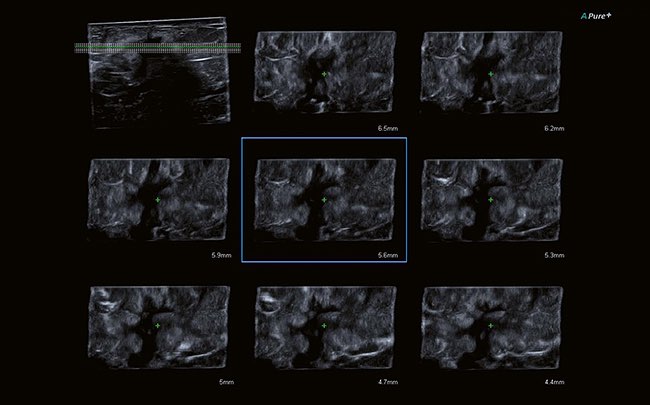

- Программно-технологический комплект 4D: рендеринг поверхности, визуализация полостей, мультипланарная реконструкция, MultiView для ультразвуковой томографии и ряд других функций

- Функция Smart Sensor 3D для большей детализации исследования

Технология Smart Sensor 3D создана для получения точных 3D-изображений. Линейный или конвексный датчики позволяют определять позицию объекта, рассчитать его объем, расстояние и угол, в том числе в режиме SMI